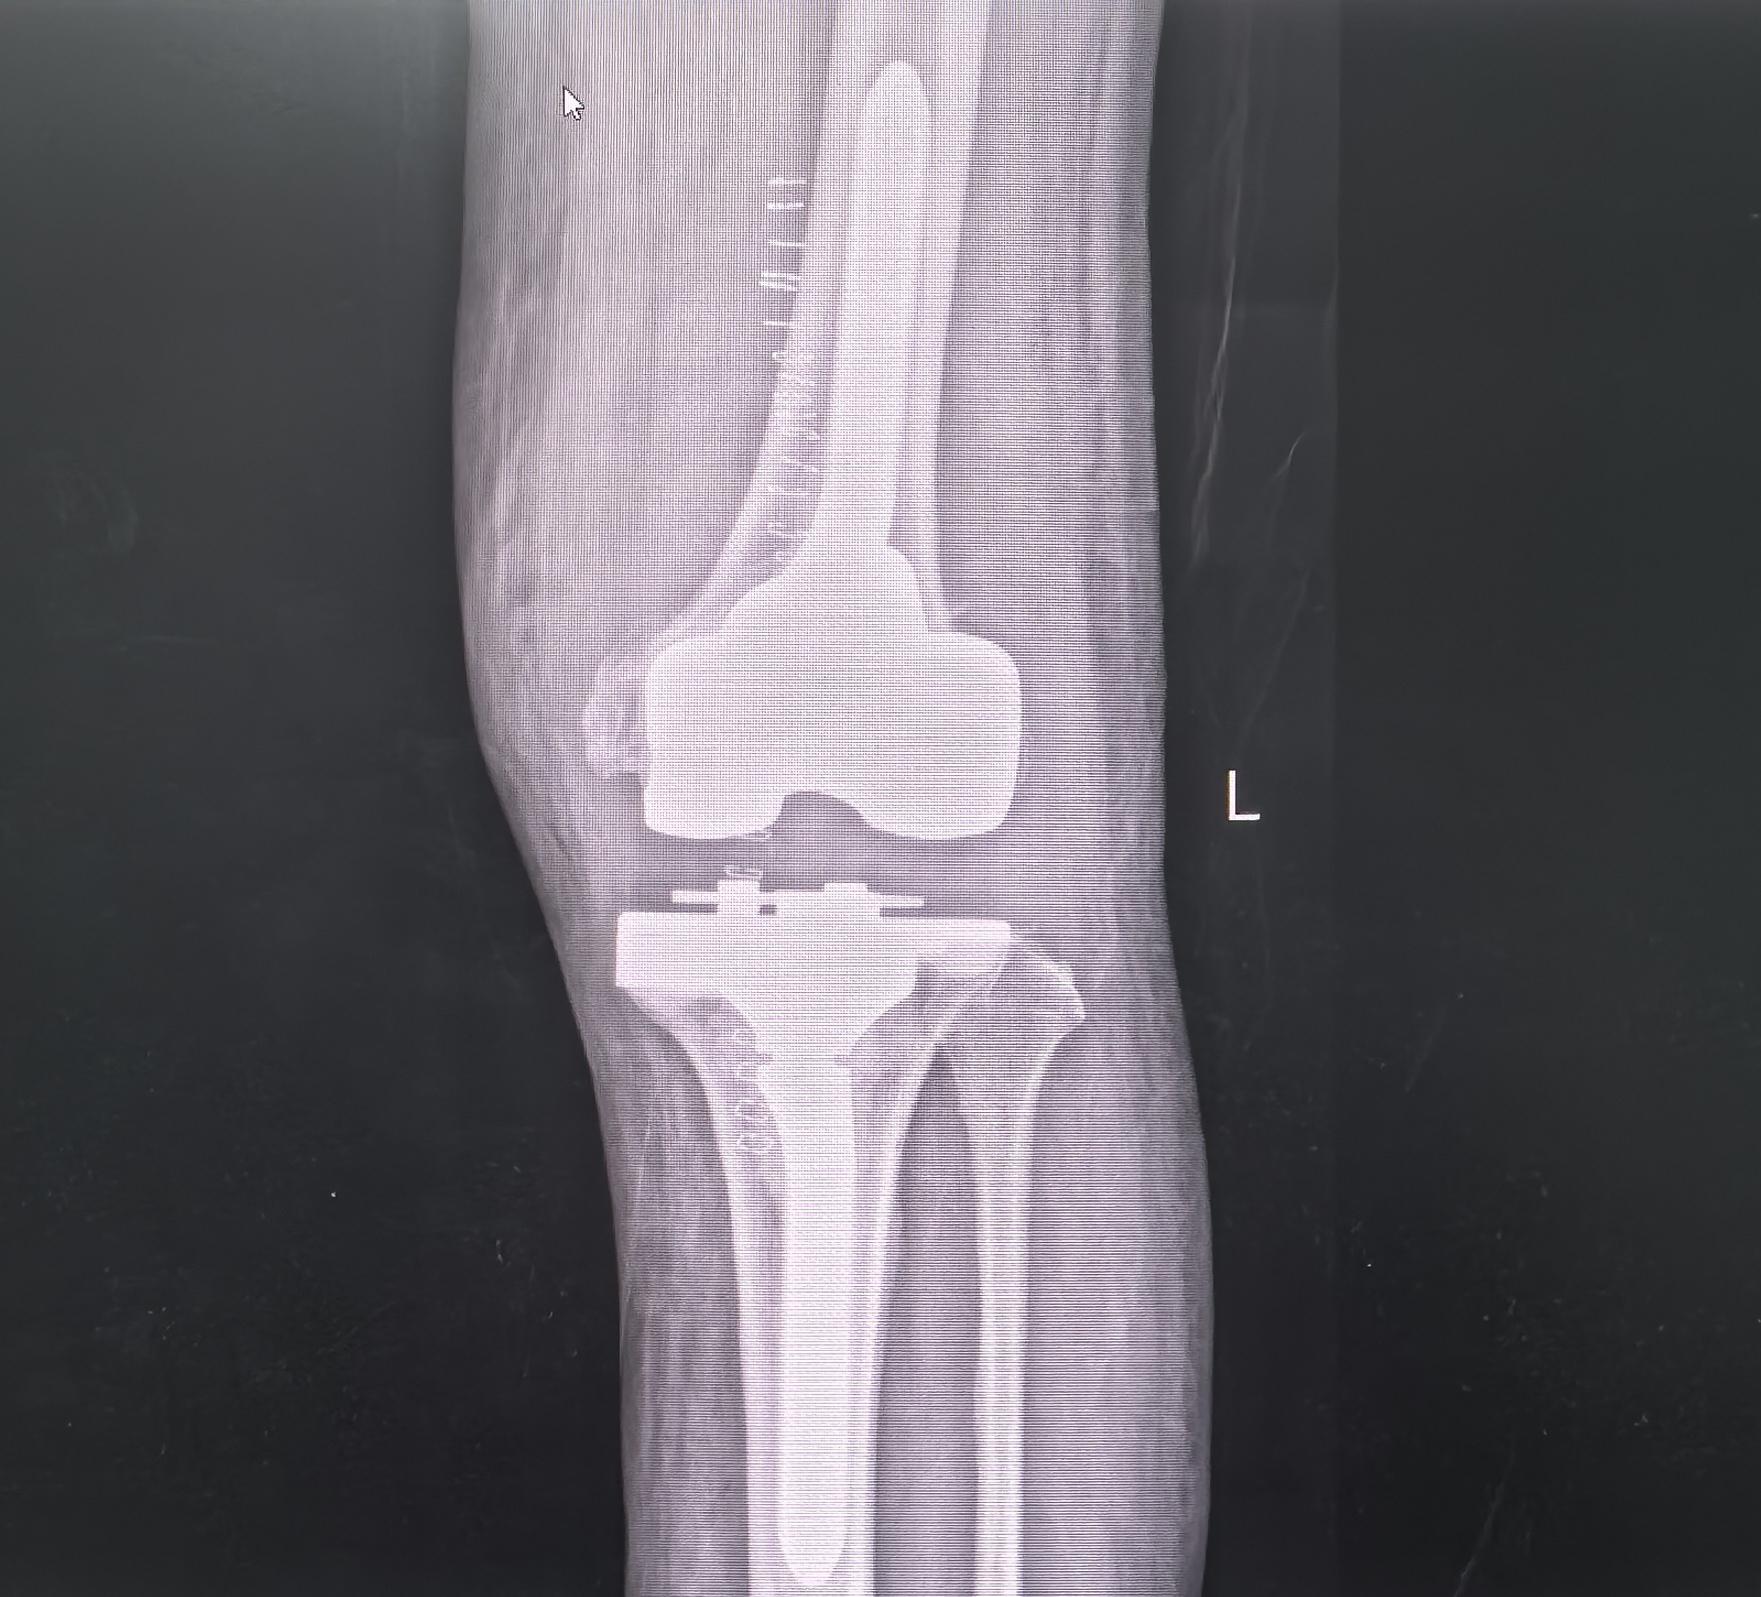

膝关节翻修。80岁老爷子,膝关节置换术后假体松动,一期翻修,再次续命20年🌹